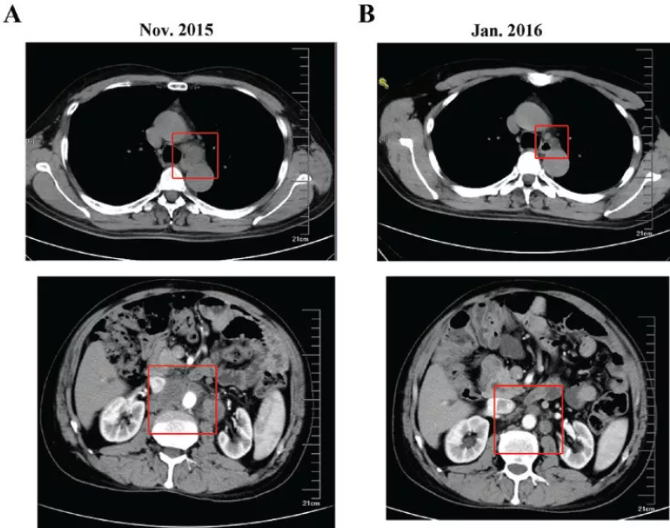

2015年11月,复查CT:纵隔、腹膜后淋巴结转移(图3)。

2016.01,复查CT示纵隔、腹膜后淋巴结缩小(图3),肿瘤标志物降低(图5)。

图3. 纵隔及腹膜后结节变化